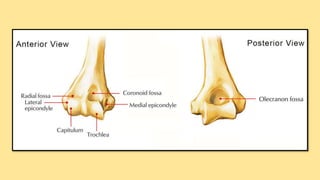

Osteology There are threebones that comprise the elbow joint: 1. The humerus 2. The radius 3. The ulna.

These bones giverise to 02 joints: HUMEROULNAR JOINT is the joint between the pulley like trochlea on the medial aspect of the distal of the humerus and the trochlear notch on the ulna. Humeroradial joint is the joint between the capitulum on the lateral aspect of the distal end of the humerus with the head of the radius. The humeroulnar and the humeroradial joints are the joints that give the elbow its characteristic hinge like

The PROXIMAL RADIOULNARJOINT is the articulation between the circumferential head of the radius and a fibro- osseous ring formed by the radial groove of the ulna and the annular ligament that hold the head of the radius in this groove. The proximal radioulnar joint is functionally a PIVOT JOINT, allowing a rotational movement of the radius on the ulna.